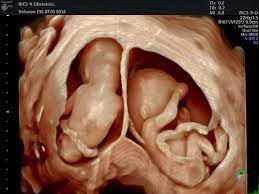

Reconstructs three-dimensional datasets from multiple 2D planes

Enables surface rendering and multiplanar reconstruction

Particularly valuable in obstetrics and cardiac imaging

A 3D volume-rendered ultrasound image showing twins in utero, demonstrating the surface reconstruction capability of modern volume imaging.